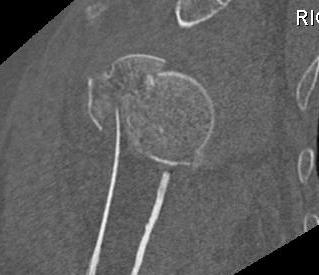

proximal humerus fracture Background ORIF with locking plate Arthroplasty Greater tuberosity fractures Lesser tuberosity fractures / avulsions Book traversal links for Proximal humerus fractures ‹ Pectoralis Major Tears Up Background ›